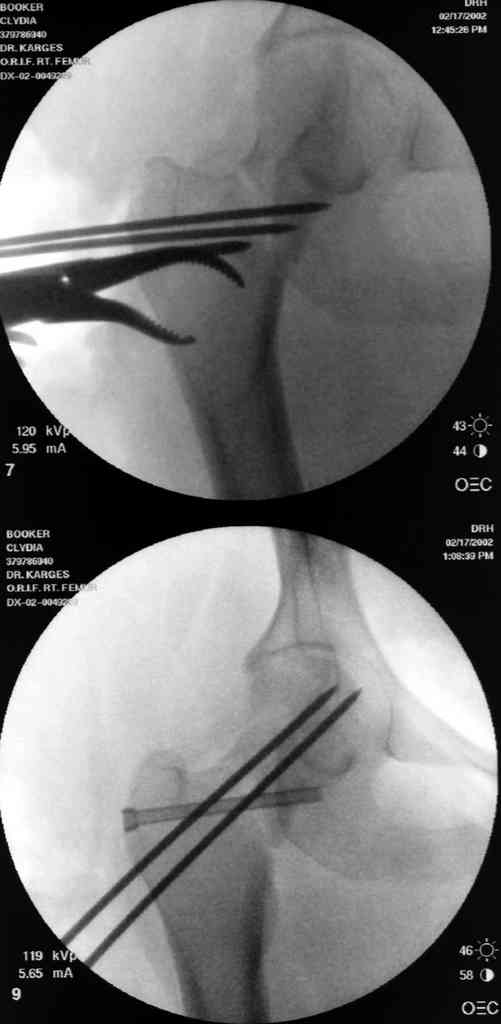

На снимках ложный сустав шейки бедра, несостоятельность фиксации. По положению шурупа можно предсказать ложный сустав, например, если screw backup за кортикальный слой около 15-20 мм, и также изменение угла от первоначального.

№2-3 типичная ошибка несоблюдения концепции параллельности шурупов, нарушение-фиксация поперечным допольнительным шурупом для приближения отломка в результате не сработало метод параллельных шурупов